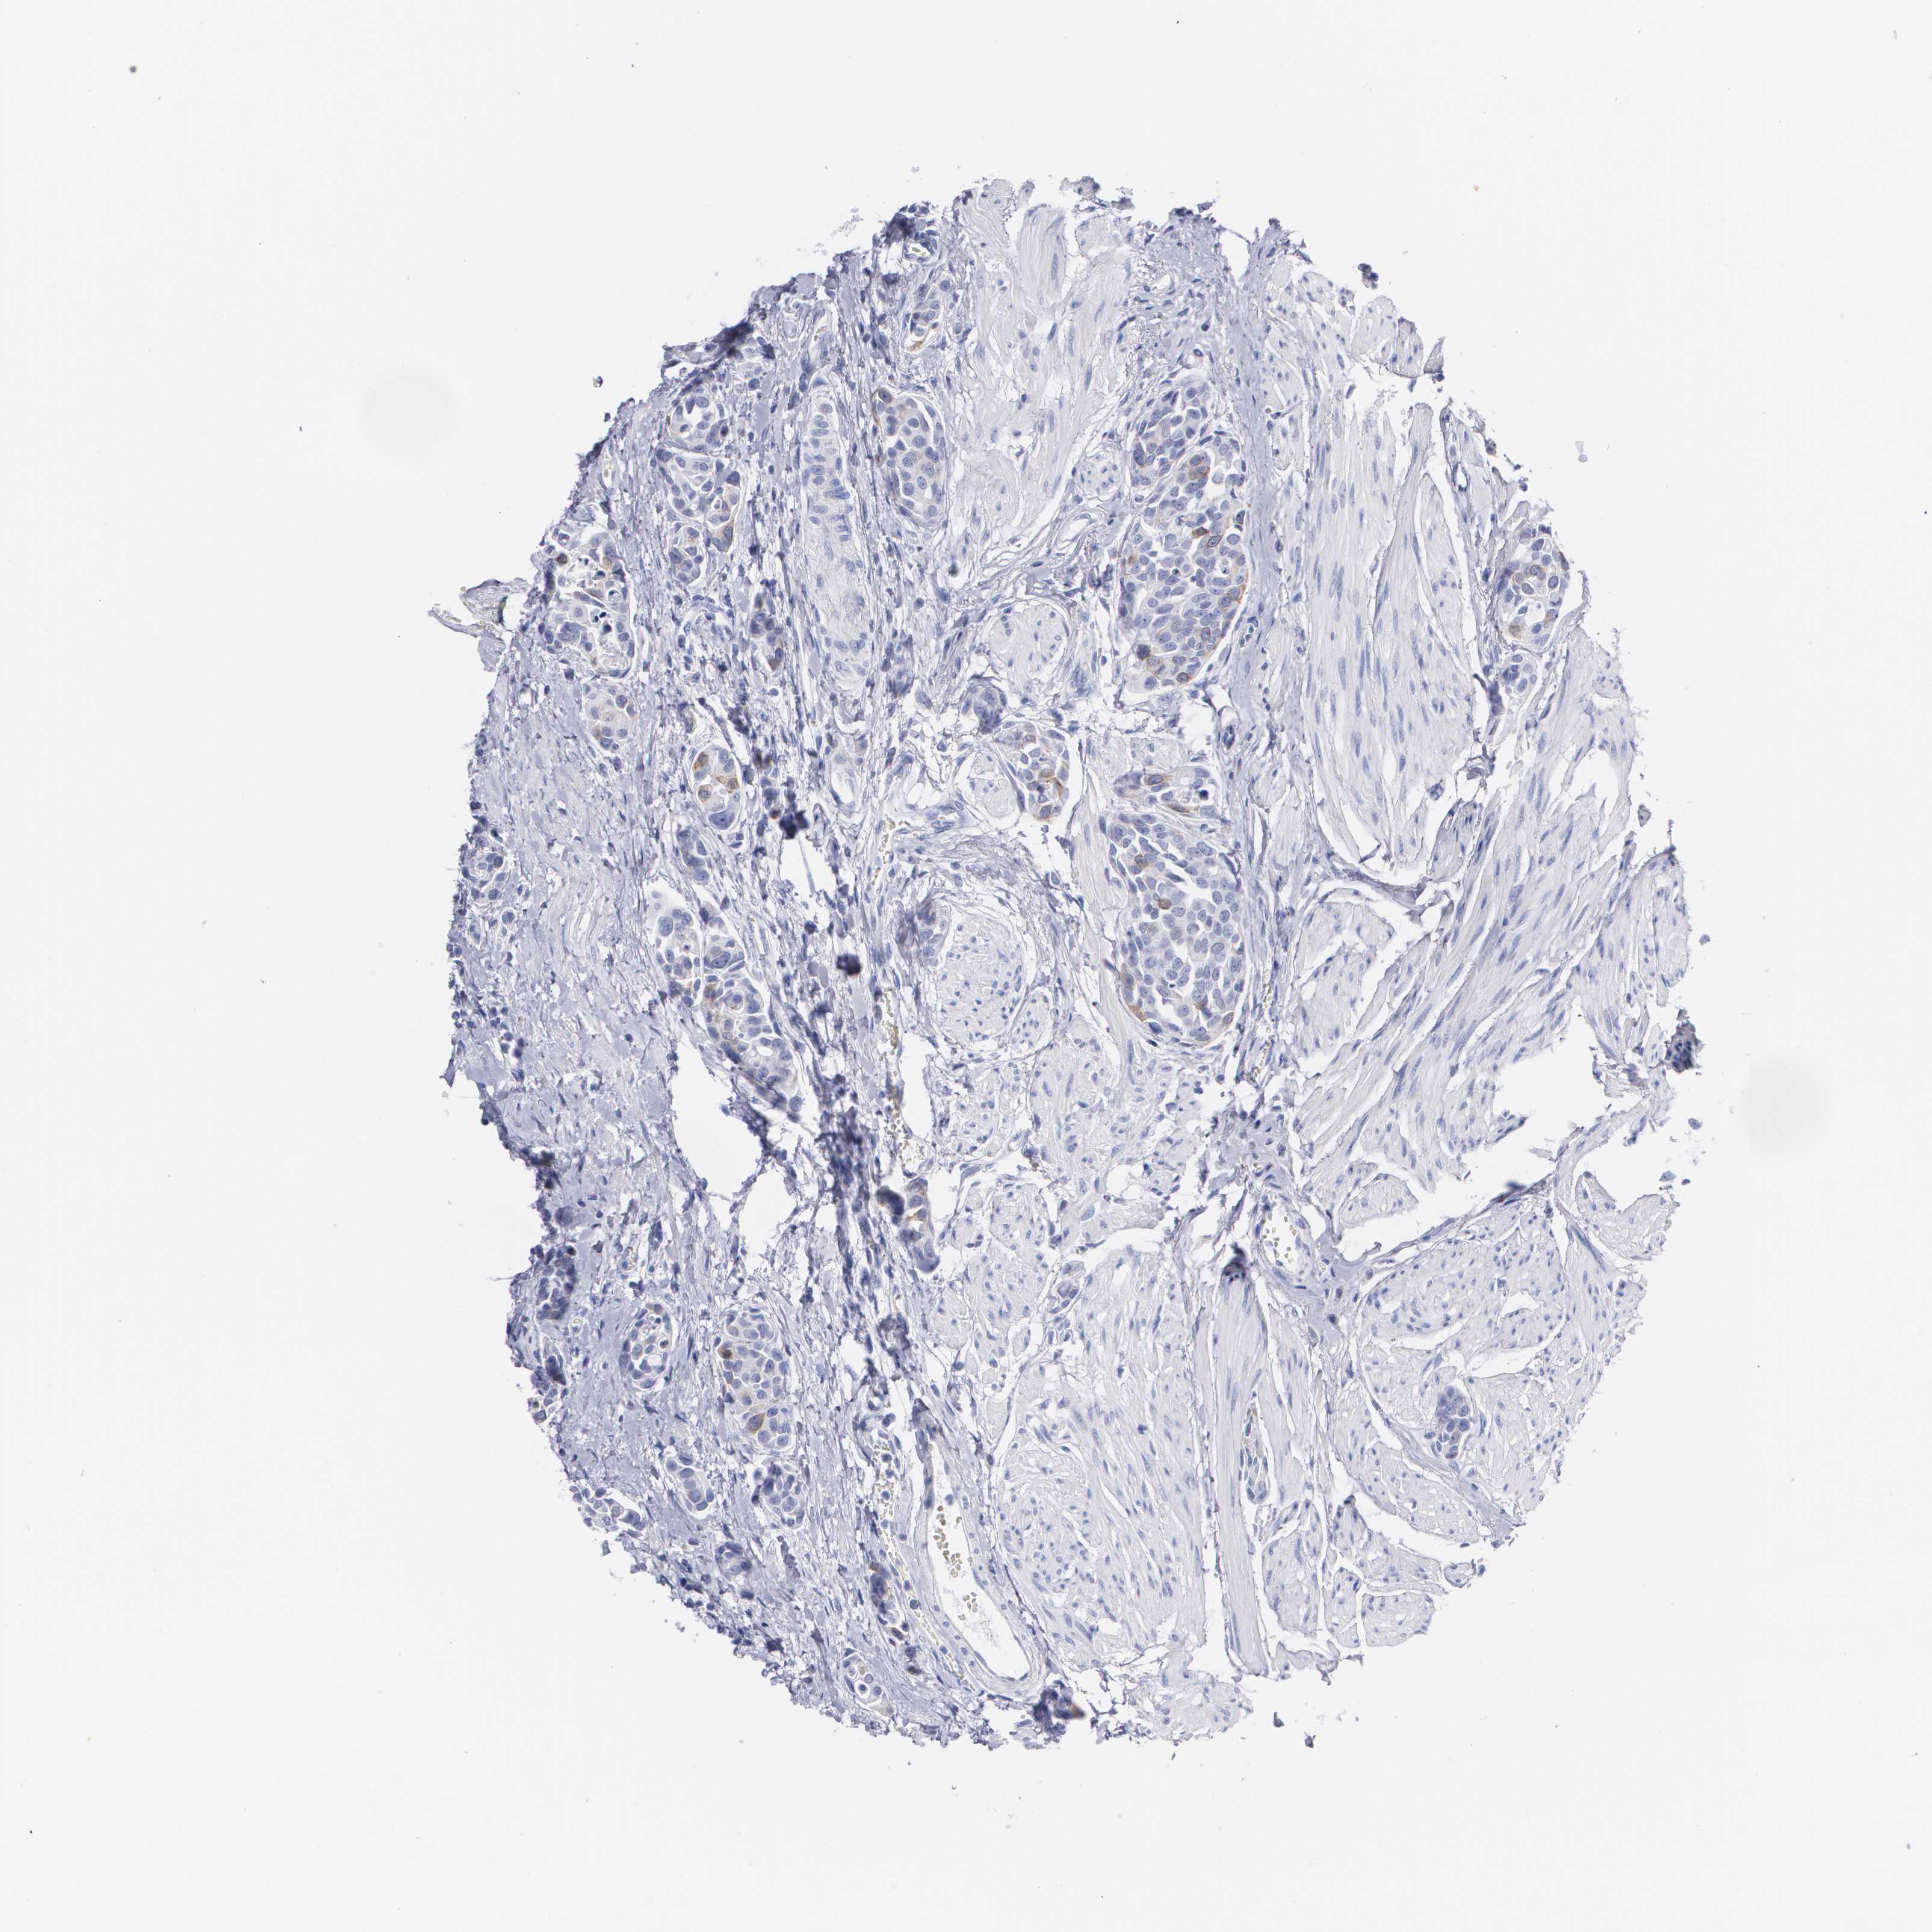

UROTHELIAL CANCER - Protein expressioni

A mouse-over function shows sample information and annotation data. Click on an image to view it in a full screen mode. Samples can be filtered based on level of antibody staining by selecting one or several of the following categories: high, medium, low and not detected. The assay and annotation is described here.

Note that samples used for immunohistochemistry by the Human Protein Atlas do not correspond to samples in the TCGA dataset.

Antibody stainingi

Antibody staining in the annotated cell types in the current human tissue is reported as not detected, low, medium, or high, based on conventional immunohistochemistry profiling in selected tissues. This score is based on the combination of the staining intensity and fraction of stained cells.

Each image is clickable and will lead to virtual microscopy that enables deeper exploration of all samples and also displays staining intensity scores, fraction scores and subcellular localization as well as patient and tissue information for each sample.

Antibody HPA040025

Antibody CAB002433

Urothelial carcinoma, High grade

Urothelial carcinoma, NOS

Urothelial carcinoma, Low grade